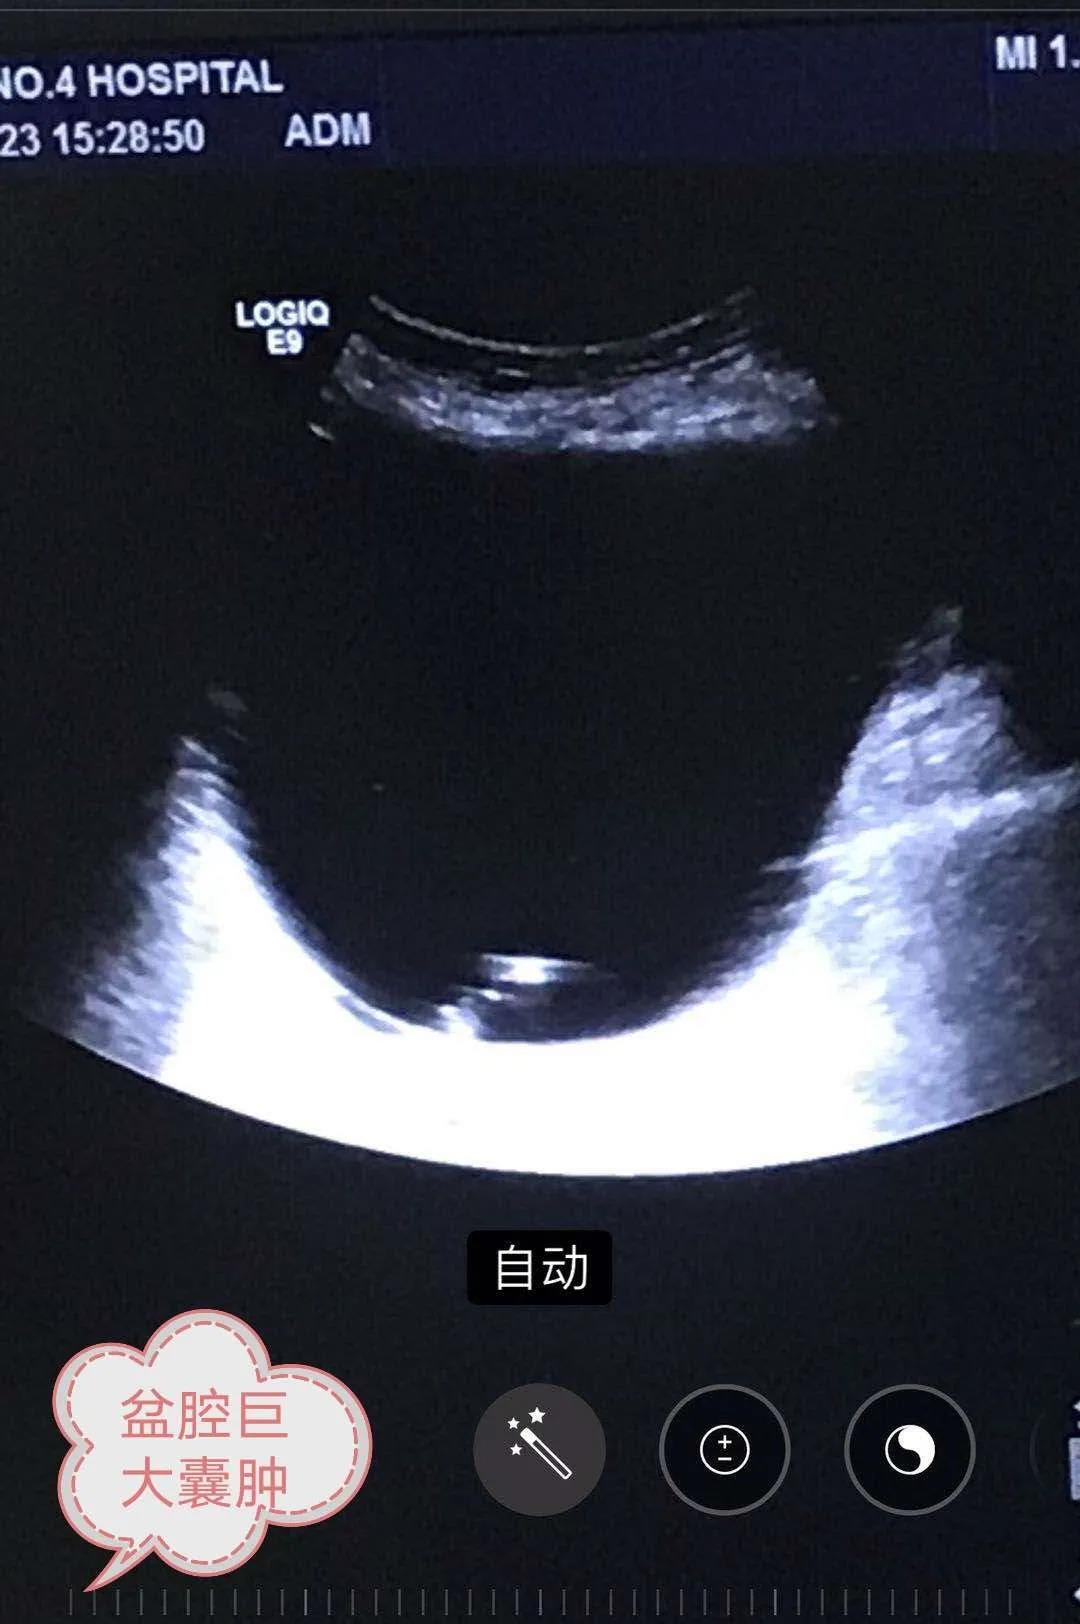

87岁的宋大娘腹胀多年,一周前于其它医院查体发现盆腔巨大囊肿,大小约15x11x9cm。子女带她来到淄博市第四人民医院外科就诊,主任弓希敏为老人仔细检查,考虑到老人高龄还有其它基础病,不适合外科手术切除囊肿。既要帮老人解决疾病痛苦,又要把创伤降到最小,经过周密考虑,弓希敏主任决定为老人实施超声引导下囊肿抽液并聚桂醇硬化治疗。超声科主任邵宏增会诊后确定了手术的可行性,并完善各项术前检查。

9月23日下午,超声引导下囊肿内置入猪尾巴管,抽得囊液1060ml,生理盐水多次冲洗并抽净,随后聚桂醇注入囊腔保留10分钟并抽净,缝合包扎,手术顺利实施,患者无不适反应。